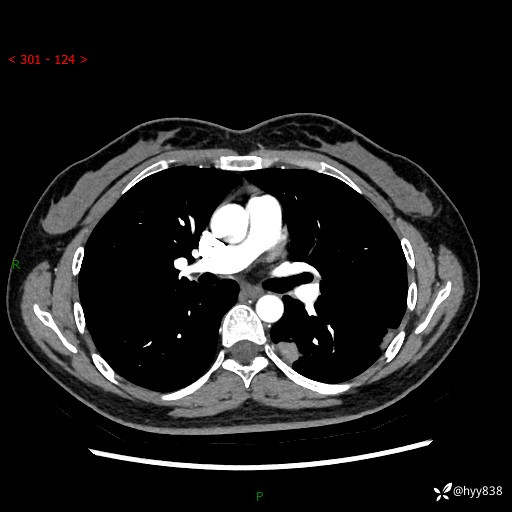

【患者信息】:36岁/女

【主诉】:左侧下胸部阵发性疼痛2周,乏力1周

【现病史及既往史】:患者自诉2周前饮酒后出现左侧下胸部阵发性疼痛,不随呼吸改变,无咳嗽咳痰、头晕头痛、咳血、呼吸困难等不适,于当地第一人民医院查胸部CT提示肺部感染,随后前往我院门诊给予抗感染(左氧氟沙星)治疗1周,自诉胸痛较前好转,感乏力、头晕,偶尔干咳,无咳痰,无发热、畏寒、胸闷、咯血、四肢酸痛、腹泻、腹痛等不适,门诊复查胸部CT提示:左肺下叶感染,病灶较前增加增大,遂以“肺部感染”收入我科。 起病以来,患者精神、饮食、睡眠可,大小便正常,体力体重无明显变化。

【检查】:胸部CT增强(外院平扫)